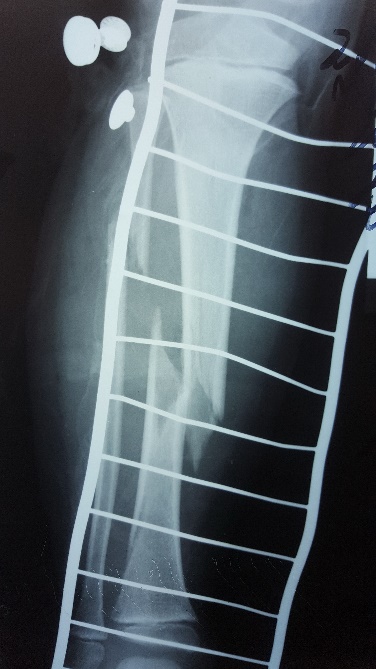

Այս ուսումնասիրությունը հիմնված է 21 հիվանդների (17 տղա, 4 աղջիկ) շարունակական խմբի բուժման արդյունքների վերլուծության վրա, որոնք ենթարկվել են տիտանե էլաստիկ մեխերով վիրահատության։ Հիվանդների տարիքը եղել է 4 տարեկանից մինչև 16 տարեկան։ 9 երեխայի մոտ կոտրվածքի պատճառ է հանդիսացել ձեռքի վրա անկումը, մնացածի մոտ կոտրվածքն առաջացել է վերջույթի ոլորման արդյունքում, վնասվածքի մեխանիզմը եղել է ուղիղ: 19 դեպքերում կոտրվածքները եղել են փակ, իսկ 2 դեպքում՝ բաց։ Ըստ վնասվածքի տեղայնացման՝ դրանք եղել են դիաֆիզար կոտրվածքներ (15 դեպք), պրոքսիմալ մետաֆիզի մակարդակի կոտրվածք (3 դեպք) և հեռավոր մետաֆիզի՝ (3 դեպք): Կոտրվածքային գծի բնույթի համաձայն՝ դիաֆիզային կոտրվածքներից հայտնաբերվել են 6 լայնակի, 4 թեք, 5 պտուտակաձև։ Մի տղայի մոտ (4 տարեկան), որի մոտ առկա էր սրունքի մ/3-ի բաց թեք կոտրվածք տեղաշարժով և մաշկի մինուս հյուսվածքներով, կատարվել է նաև վերքերի առաջնային վիրաբուժական մշակում և կարում՝ ռետինյա արտաթորիչներով։ Սակայն մի քանի շաբաթ անց սկսվել է մաշկի նեկրոզ։ Այդ իսկ կապակցությամբ կատարվել է երկրորդ վիրահատական միջամտությունը։ Կատարվել է մաշկի աուտոտրանսպլանտացիա։ Մաշկի կտորները վերցվել են առողջ ազդրի առաջային մակերեսից: (Նկ 1)

Երեխաները վիրահատված վերջույթը սկսել են օգտագործել առօրյա կյանքում (սնվել, հագնվել, հիգիենայի պարագաներ օգտագործել) օստեոսինթեզից 10-12 օր հետո։ Դպրոց հաճախելը վերսկսվել է հիվանդանոցից դուրս գրվելուց 7-10 օր հետո: Վիրահատված վերջույթի շարժման տիրույթի ամբողջական վերականգնում նկատվել է բոլոր երեխաների մոտ վիրահատական բուժումից 4-5 շաբաթ անց՝ անկախ կոտրվածքի բնույթից։ Սպորտին վերադարձը տեղի է ունեցել վիրահատությունից հետո 6 շաբաթից մինչև 3 ամիս ընկած ժամանակահատվածում՝ կախված սպորտի տեսակից և կոտրվածքի բնույթից։ Ինտրամեդուլյար մեխերի հեռացումը կատարվել է 15 դեպքերում օստեոսինթեզից 6 և ավելի ամիս անց, իսկ մնացած դեպքերում 12 ամիս անց։ Իմպլանտը հեռացվել է ընդհանուր անզգայացման տակ։ Իմպլանտի հեռացման ընթացքում կամ դրանից հետո բարդություններ չեն եղել: Բուժման ավարտից և իմպլանտների հեռացումից հետո հիվանդների արդյունքները գնահատելիս բոլոր դեպքերում գրանցվել է գերազանց արդյունք։ Հանդիպած բարդություններից եղել է 2 դեպք։ Մեկը՝ մաշկի նեկրոզ, որը պայմանավորված էր մեծ վերքի առկայությամբ կապված վնասվածքի բնույթից (ավտովրաերթ), և երկրորդը՝ ձողով մաշկի պերֆորացիա և թարախակալում։